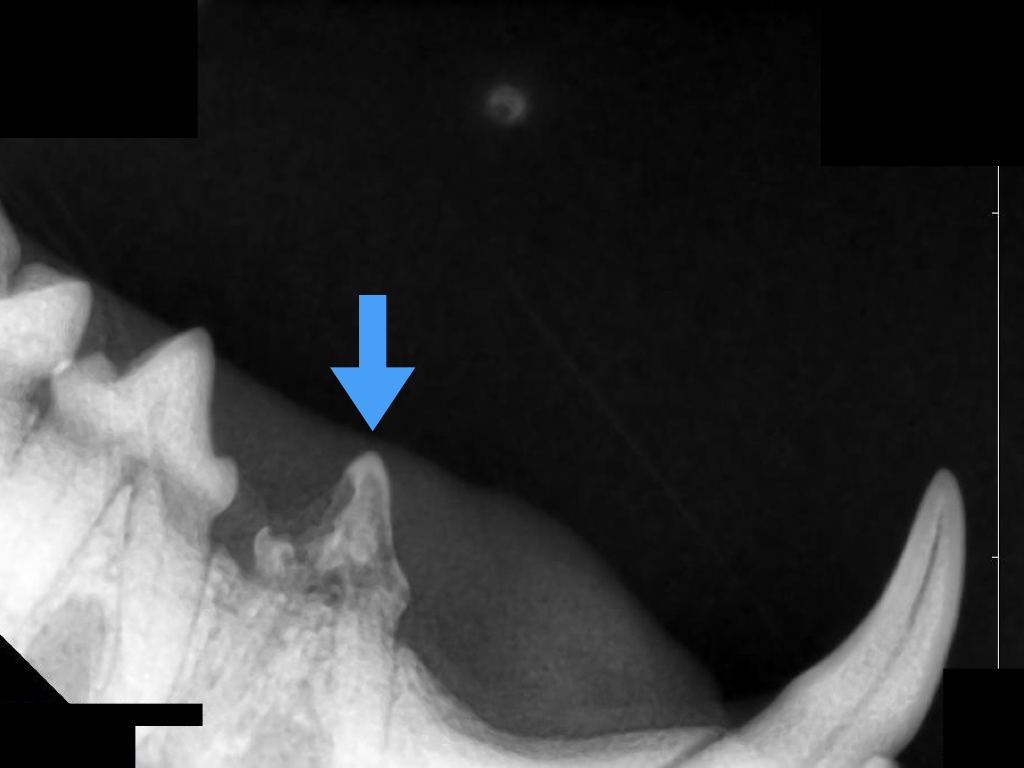

吸収病巣は歯の内部で進行する病気のため、見た目だけでは正確な診断ができません。

歯科用レントゲンを撮影することで、病変の範囲や進行度、治療方針が明確になります。

AVDCの分類に基づき、ステージ(進行度)とタイプ(吸収の形)を評価します。